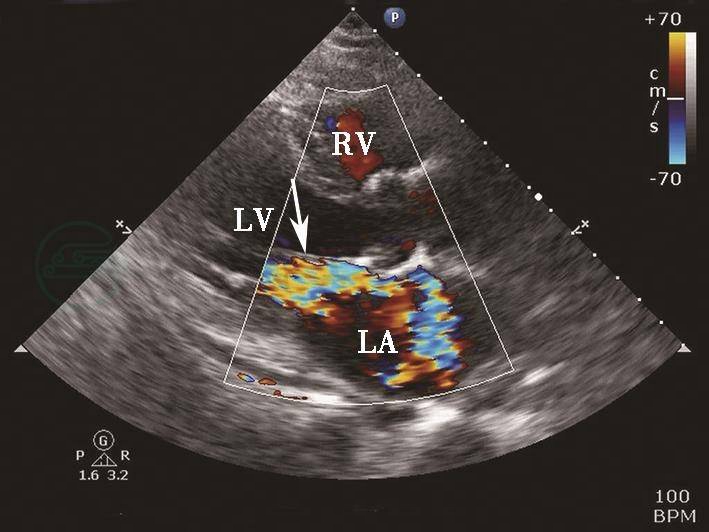

图7心肌梗死二尖瓣乳头肌断裂彩色多普勒血流图像

彩色多普勒血流图像显示二尖瓣乳头肌断裂导致重度偏心性反流(箭头示)。LA.左心房;LV.左心室;RV.右心室。